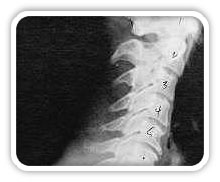

Phase One Subluxation Degeneration

Phase One Subluxation Degeneration is seen in subluxations that have been present for up to twenty years. This phase is characterized with a loss or change in the normal curve in the spine. On this example you can see that the normal forward (lordotic) curve is lost. This spine even has developed a reverse curve in the neck. The disc spaces have also begun to exhibit a slight change in shape. One good point is that the bodies of each of the vertebrae (the square part in front) still exhibits clean clear borders. Segmental motion may be abnormal but overall motion is probably not affected. Chiropractic reconstructive care for a phase one can take from 6 to 18 months. More than 80% of people with Phase One Subluxation Degeneration have no pain. Therefore, if left uncorrected, phase one continues to progress with time until it eventually reaches the next phase.